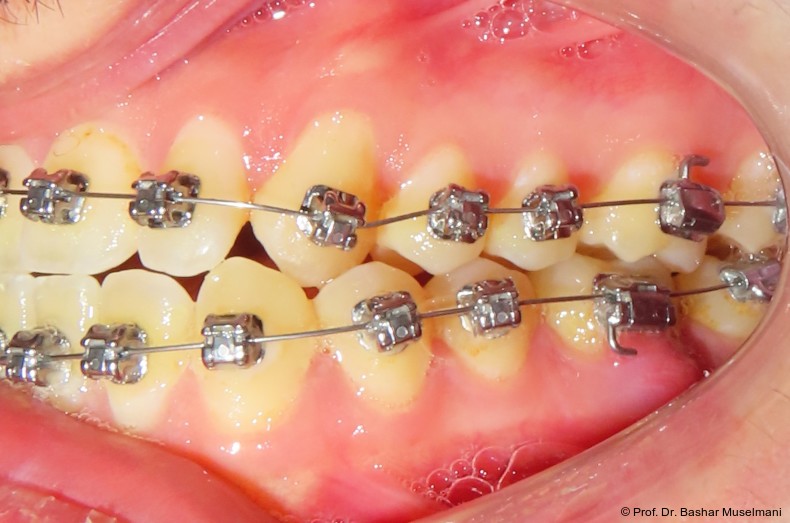

Die Abbildungen 1 bis 3 zeigen die initiale klinische und radiologische Ausgangssituation.

Zu Beginn der Nivellierungsphase wurden in beiden Kiefern 0.013" CuNiTi-Bögen eingesetzt (Abb. 4a–e).

Diese Sequenz ermöglichte eine schrittweise Ausformung der Zahnbögen, eine kontrollierte Torque-Expression sowie eine präzise Feineinstellung in der Abschlussphase (Abb. 5a–e).